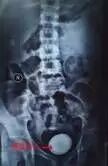

家住南昌市新建县的吴XX,是一名17岁的少年郎,近3年来没有任何征兆的感到下腹胀痛并出现尿频和血尿等症状,时常间断性发作,家人意识到事情严重性,当即到当地医院检查,诊断为“肾结石”,经消炎治疗后,症状后有所缓解,但这些症状时常出现,严重影响了他的学习和生活,正当他为此一筹莫展的时候,一次偶然的机会,经人介绍和家人一起来到南昌结石病专科医院寻求帮助,我院医师当即为其做了详细的检查,是一个巨大的膀胱结石,其父亲在拿到报告单时,感叹的说:“还好到了结石专科,真是害死人呀,这哪里是肾结石,明明是这么大的膀胱结石”。

为了让患者早日解除病痛,经病例讨论后,于2016年3月21日上午行“膀胱切开取出术”,取出一枚大小约“6*3cm”大小的结石,看到结石,患者和家属都大吃一惊,“像这么大的结石长在身上,还是第一次看到,看病还是要到专科,悬着的心总算落地了”,并对医院的服务和主治医师孙医师的诊疗技术表示感谢。